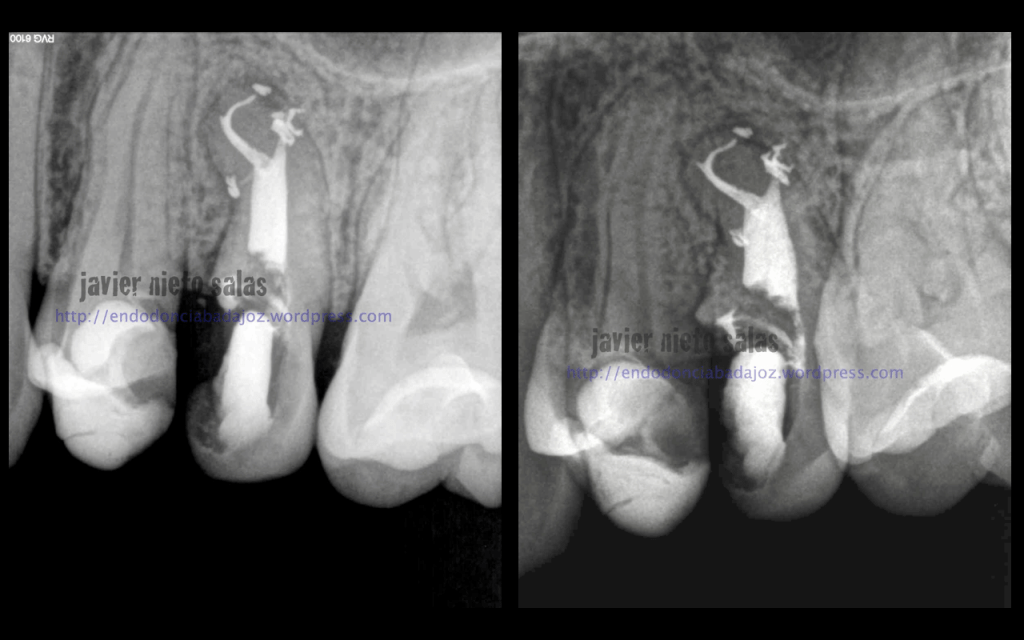

En el  primer caso de hoy, podemos ver la importancia de pararse a ver la radiografía inicial, el tamaño de la lesión y el posible origen, algo, a mi parecer, bastante importante.

Así pues, en esta primera imagen vemos la lesión lateral que nos hace sospechar de una posible salida a ese nivel. Modificando nuestra técnica de limpieza y obturación: